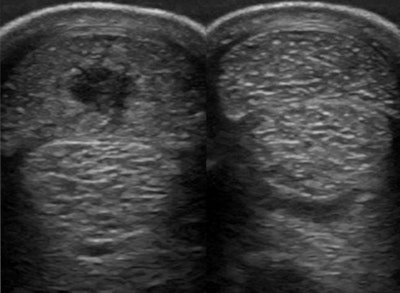

Superficial digital flexor tendon injury; abnormal tendon on the left, normal tendon on the right. Image courtesy of Sarah Boys-Smith.

Superficial digital flexor tendon injury; abnormal tendon on the left, normal tendon on the right. Image courtesy of Sarah Boys-Smith.Injuries can also occur in horses competing in more sedate sports.

"Both high-speed work and jumping can put a critical load on the tendon structure," Boys-Smith commented. "Ultrasound is used to look for enlargement of the tendon, find lesions within the tendon, and identify any loss or disruption of the fiber pattern within the tissue."